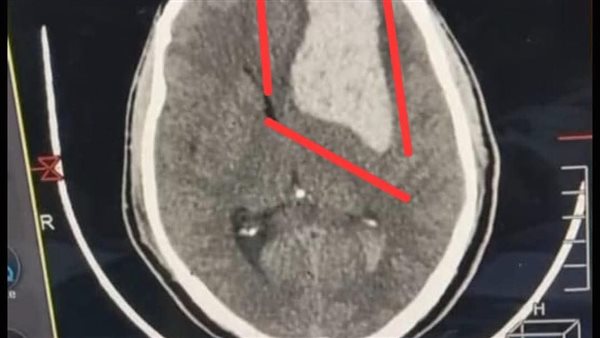

وبمجرد وصول الشاب، خضع لفحص الأشعة المقطعية التي أظهرت وجود نزيف عميق داخل النسيج المخي، وهو نوع خطير من النزيف قد يؤدي إلى فقدان الوعي الكامل وتعطل الوظائف الحيوية إذا لم يتم التعامل معه سريعًا. تم نقل المريض مباشرة إلى قسم العناية المركزة وتجهيز كميات مناسبة من الدم والبلازما استعدادًا للجراحة، والتي وصفت من قبل الفريق الطبي بأنها واحدة من العمليات الدقيقة التي تتطلب خبرة عالية وتركيزًا بالغًا.